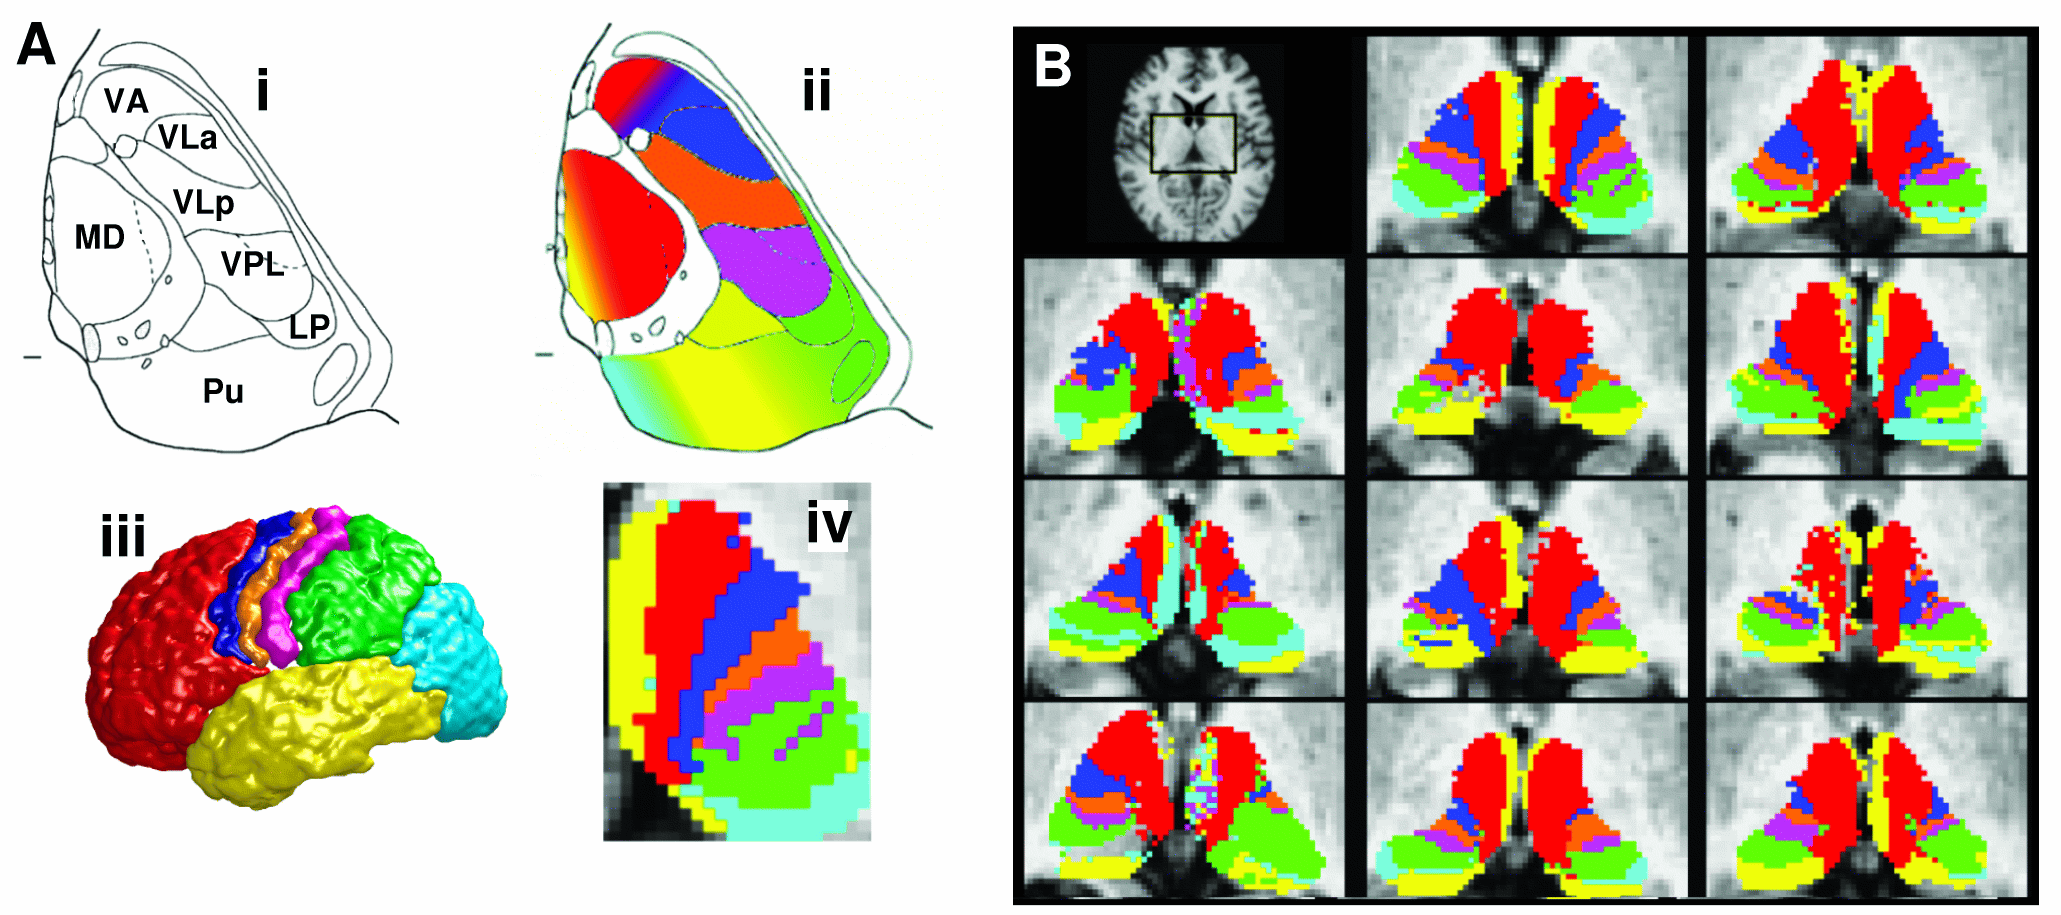

To estimate the voxelxROI connectivity probtrackx quantifies connectivity values between each voxel in a seed mask and any number of user-specified target masks. In the example above, seed voxels in the thalamus are classified according to the probability of connection to different cortical target masks.